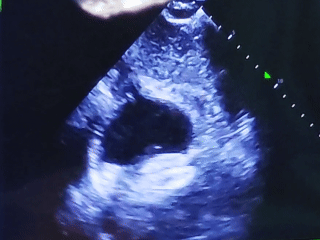

超声诊断:房间隔中部组织薄弱,随整个心动周期膨向右房,膨出基底部宽29.7mm,膨出幅度8.1mm,中部组织见连续中断,断端回声增强,CDFI示:心房水平左向右分流,分流束宽14.7mm,分流峰速119cm/s,压差:6mmHg;剑下切面:缺口宽19.2mm,上腔残边12.7mm,下腔残边12.2mm,下腔边为膨出软边;胸骨旁四腔切面见两孔:其中一个孔宽7.9mm,另一个孔宽15.0mm,两孔间距8.4mm,前下残边7.1mm,后上残边6.2mm;大动脉短轴切面见两孔:其中一个孔宽9.6mm,另一个孔宽15.4mm,两孔间距6.3mm,大动脉残边无边,后下残边6.0mm。室间隔连续完整,CDFI示:未见过隔分流。

在超声下观察房缺封堵器形态

双孔房缺,术前彩超报两孔分别7.9mm和15.0mm,孔距6.3-8.4mm,选择MemoCarna氧化膜房缺封堵器DMFQFDQ-I 28,封堵后仍有2-3mm残余分流,对血液动力学没有影响,术者评估在允许范围

术后观察封堵器形态

左心耳封堵器稳定锚定在心耳内部

房缺封堵器稳定夹持房间隔